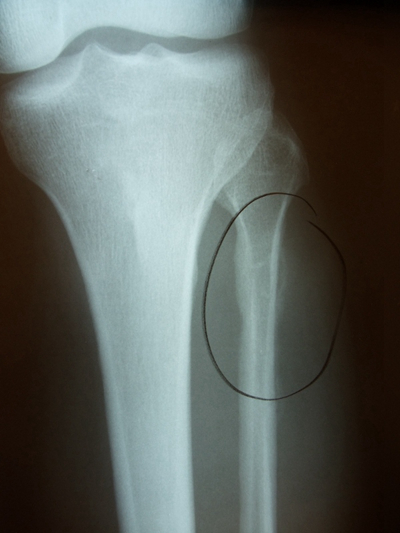

骨折圖片